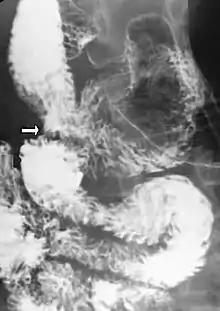

Diagnosis is very difficult, and usually one of exclusion. SMA syndrome is thus considered only after patients have undergone an extensive evaluation of their gastrointestinal tract including upper endoscopy, and evaluation for various malabsorptive, ulcerative and inflammatory intestinal conditions with a higher diagnostic frequency. Diagnosis may follow X-ray examination revealing duodenal dilation followed by abrupt constriction proximal to the overlying SMA, as well as a delay in transit of four to six hours through the gastroduodenal region. Standard diagnostic exams include abdominal and pelvic computed tomography (CT) scan with oral and IV contrast, upper gastrointestinal series (UGI), and, for equivocal cases, hypotonic duodenography. In addition, vascular imaging studies such as ultrasound and contrast angiography may be used to indicate increased bloodflow velocity through the SMA or a narrowed SMA angle.[14][15]

- Upper gastrointestinal series showing extreme duodenal dilation (white arrow) abruptly preceding constriction by the SMA.